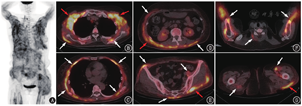

患者女,64岁,主诉发现臀部结节1年,皮疹8个月,发热6个月。患者1年前左侧臀部无明显诱因出现质硬结节,后因频繁搔抓导致局部皮肤破损,伴结节红肿、触痛,当地医院予抗生素治疗后症状未缓解。8个月前患者左侧臀部皮损较前明显增大,同期出现额部、眼睑及双上肢皮疹,伴乏力,外院予外用及口服药物治疗(具体不详)后皮疹逐渐消退。7个月前患者于当地医院行左侧臀部皮损清创术,术后病理提示:皮肤表面溃疡,皮下纤维组织增生及急、慢性炎性细胞浸润。清创术后患者臀部伤口未愈合,再行负压引流(vacuum sealing drainage, VSD)联合游离皮瓣移植术后创面愈合。6个月前患者出现间断发热,最高体温39.3 ℃,每日3~4个热峰,伴乏力、全身肌肉酸痛和右侧膝关节肿痛,外院反复抗感染治疗后症状无明显改善。既往史:患者10年前诊断为原发性高血压,规律服用降压药物,血压控制水平可。家族史:丈夫患有髋关节结核,孙女曾患结核性胸膜炎。患者为进一步诊治就诊本院,入院后查WBC计数10.46(括号内为正常参考值范围,下同;3.50~9.50)×109/L,C反应蛋白(C-reactive protein, CRP) 154.40 (>8.00;提示急性炎性反应) mg/L,肌酸激酶(creatine kinase, CK) 25(24~170) U/L,血培养阴性,类风湿因子、抗核抗体、抗中性粒细胞胞质抗体阴性,肿瘤标志物正常。双大腿MRI提示双侧臀部、髋关节周围及大腿各组肌肉多发异常信号,考虑炎性病变可能。体格检查四肢近端肌肉压痛明显。临床为排查肿瘤并明确发热原因行18F-FDG PET/CT显像(图1),结果示躯干和四肢近端骨骼肌代谢弥漫不均匀增高,肌肉周围筋膜代谢增高更明显,部分受累肌肉密度略减低,SUVmax 8.4;受累肌肉周围皮下脂肪间隙可见多发代谢增高的软组织影及条索影,SUVmax 7.3;另外双肺可见少许陈旧性斑片、条索影,双肺门及纵隔可见炎性淋巴结,密度较高,部分伴钙化,SUVmax 5.9;甲状腺右叶亦见一代谢增高的结节,SUVmax 13.7,考虑为甲状腺原发病变,建议患者进一步行超声检查。

本例患者就肌肉病变的影像特征来看,要考虑炎性病变的可能。患者之后行肌电图提示双下肢可疑肌源性损害,肌炎相关抗体抗黑色素瘤分化相关基因5(melanoma differentiation associated gene 5, MDA5)抗体阳性。临床诊断为抗MDA5抗体阳性的皮肌炎,予足量激素联合甲氨蝶呤治疗后,患者体温逐渐恢复正常,四肢近端肌肉压痛好转,炎性指标也降至正常范围。20d后,患者再次出现发热,最高体温39.0 ℃,CRP 302.71 mg/L,血二代测序(next-generation sequencing, NGS)检测到结核分枝杆菌。为进一步明确诊断,患者行右侧股四头肌活组织检查,病理提示肌肉组织炎性改变,肌纤维变性、坏死,局灶肌外膜及肌束间可见淋巴细胞及中性粒细胞浸润,可见较多抗酸及弱抗酸染色阳性的杆菌,考虑结核感染。最终临床诊断为皮肌炎合并血流播散性结核,考虑发热与结核感染相关,加用五联抗结核治疗后患者症状明显改善。由于特殊的免疫基础及长期接受激素和免疫抑制剂治疗,皮肌炎患者也容易合并各种感染[11]。特发性炎性肌病住院患者的感染发生率为27.6%,其中细菌感染是最常见的感染类型[12]。值得注意的是,特发性炎性肌病合并分枝杆菌感染的发生率为3.69%,以结核分枝杆菌最常见;播散性结核病(46.58%)和肺结核(49.07%)的发生率相当,且肌肉受累较为常见,可能的原因为结核分枝杆菌容易在特发性炎性肌病患者变性或坏死的肌肉组织中种植[6,13]。本例患者的肌肉病变不完全符合皮肌炎多对称受累的特点,并且肌肉周围的筋膜受累比肌肉本身更重,因此PET/CT显像上的病变特点还是要考虑合并感染的可能,皮肌炎合并肌肉感染能够解释本例全貌。